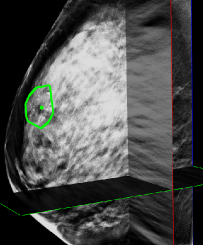

One application of such a knowledge transfer problem is the detection of microcalcification (MC) groups in 3D digital breast tomosynthesis (DBT). A MC group is composed of multiple small and similar individual MCs, and is considered a possible sign of breast cancer. Because MCs may be small and lack enough contrast (as in Figure 1(a)), they can be easily missed by radiologists during the routine screening process. Needless to say, a MC group computer-aided detection (CAD) can help radiologists locate suspicious regions and help them make diagnostic decisions.

A large number of literature has been reported on creating CAD system for MC groups in 2D mammography (as in Figure 1(a)). However, publications on CAD for recently emerged DBT (as in Figure 1(b)) are very limited. This is due to the difficulty of collecting enough cancer cases to train a DBT CAD from scratch. Instead, most researchers built systems on small DBT datasets with limited training [1, 2] or applied a mammography CAD directly on slices or projections of DBT volumes [3, 4, 5].

The 3D DBT provides additional depth information. However, due to the limited angle of X-ray source used in reconstruction, the resolution of the depth is much worse than the resolution within each DBT slice.

Hence obvious steps are made to adapt 2D mammography solution to 3D DBT without retraining or fine-tuning the system with limited DBT data. The modifications of the 2D system include making 2D candidate generator work slice-by-slice and change the scopes and to be in 3D. With the dimension change of the scopes, all the appearance features are now computed in 3D, except the shape and distribution descriptors are still computed in a 2D fashion with the depth information of the candidates ignored.

4.2 Performance on DBT Volume Image

The proposed system was tested on an independent GE SenoClaire DBT volume set with 23 labeled malignant MC groups and 42 normal cases, no individual MC labeled and no other abnormalities visible. Figure 4(a) shows the MC group detection FROC and the comparison with other previously published MC group detection performances on DBT [1, 2, 3, 4, 5, 10]. Figure 4(b) shows two successful detections. The proposed system shows state-of-the-art performance compared with these published works, although all these works including ours were tested on different and relatively small datasets ( cancerous lesions). We need to emphasize that there was absolutely no training or fine-tuning on the DBT data for our system, while other works were not restricted to develop on small numbers of DBTs that could cause overfitting. The study from Morra et al. [10] reported better performance, but the authors used Hologic cases with two-view DBT volumes per breast, which may double the chance to find MC groups, while the GE set we were using had only one DBT view available. Furthermore, there is no method details disclosed in [10].